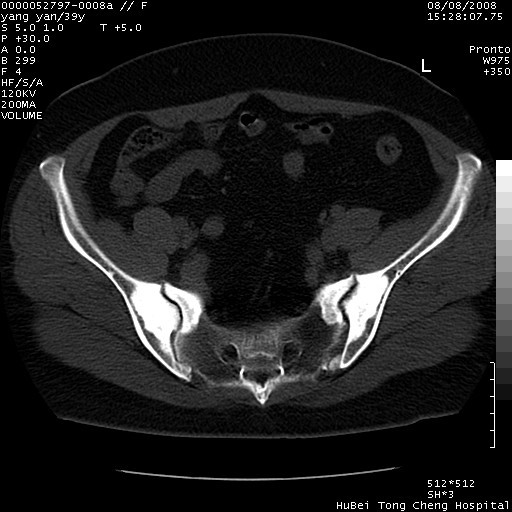

患者 女,39岁。因外伤检查,偶然发现。

典型!双侧骶髂关节致密性骨炎。

典型!病变主要累及双侧髂骨。常见于育龄期妇女。

致密性骨炎,一般不跨越关节面,可是这个骶骨关节面也有硬化。

髂骨致密性骨炎系一种以骨质硬化为特点的非特异性炎症,有高度致密的骨硬化现象,尤其以髂骨下2/3更为明显,但关节间隙则无改变。因位于骶髂关节,且该关节症状明显,故又称之为“骶髂关节致密性骨炎”。 本病90%以上为中年女性,以妊娠后期、尤其分娩后为多见,亦可见于尿路或女性附件慢性感染后,或盆腔内其他感染。此外,臀骶部的外伤亦可诱发或引起本病。  妊娠、分娩及外伤均可引起骶髂关节韧带的撕裂而易使局部的血供受阻。因此早期局部呈现充血、水肿及渗出增加等,渐而局部出现增生与变性反应,随着胶原纤维的致密化而向硬化演变;血管形成厚壁血管,易闭塞而引起髂骨耳状面处缺血和缺氧,骨质呈现硬化性改变,以致手术时局部出血较少。骶髂关节囊壁显示纤维增生、弹性降低及松动样改变。继发于盆腔内炎症者亦出现相类似的病理改变,可能系细菌内毒素作用所致。